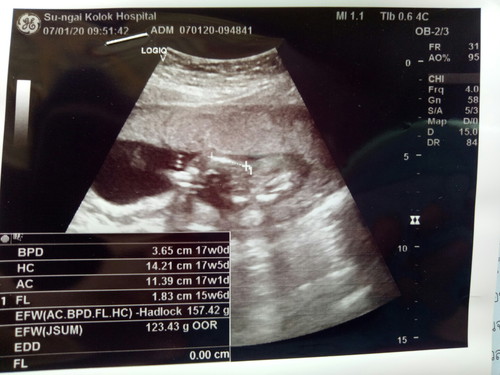

แม่ๆดูออกกันไหมค่ะ ผู้ชายหรือผู้หญิง อีแม่อยากได้ผู้หญิง?? น้ำหนักลูกเท่าไรคะ แม่ท้องแรกค่ะ

ดูเพศไม่เห็นค่ะ ไม่ชัด น้องหนัก123กรัมค่ะ EFWคือน้ำหนักค่ะ